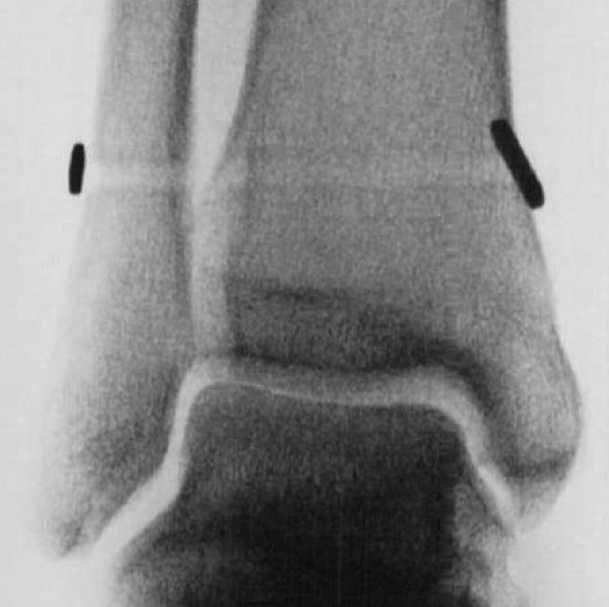

The two bones of the leg (tibia and fibula) are connected just above the ankle by strong ligaments. This connection is called the ankle syndesmosis. It allows a small amount of movement between the leg bones during activities.

See images below

Weight-bearing X-rays comparing both ankles are useful, with MRI, weight-bearing CT and even ankle arthroscopy sometimes required to determine whether the syndesmosis is stable or unstable (see images below).